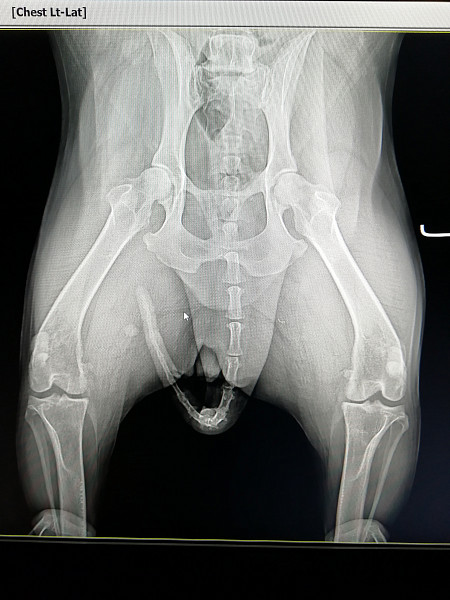

Рак тазобедренного сустава: симптомы, лечение, прогноз и фото

Рак тазобедренного сустава: симптомы саркомы, прогноз срока жизни при метастазах в подвздошной кости, опухоль в суставе . Рак тазобедренного сустава является редким заболеванием .